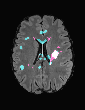

In recent years, data-driven machine learning (ML) methods have revolutionized the computer vision community by providing novel efficient solutions to many unsolved (medical) image analysis problems. However, due to the increasing privacy concerns and data fragmentation on many different sites, existing medical data are not fully utilized, thus limiting the potential of ML. Federated learning (FL) enables multiple parties to collaboratively train a ML model without exchanging local data. However, data heterogeneity (non-IID) among the distributed clients is yet a challenge. To this end, we propose a novel federated method, denoted Federated Disentanglement (FedDis), to disentangle the parameter space into shape and appearance, and only share the shape parameter with the clients. FedDis is based on the assumption that the anatomical structure in brain MRI images is similar across multiple institutions, and sharing the shape knowledge would be beneficial in anomaly detection. In this paper, we leverage healthy brain scans of 623 subjects from multiple sites with real data (OASIS, ADNI) in a privacy-preserving fashion to learn a model of normal anatomy, that allows to segment abnormal structures. We demonstrate a superior performance of FedDis on real pathological databases containing 109 subjects; two publicly available MS Lesions (MSLUB, MSISBI), and an in-house database with MS and Glioblastoma (MSI and GBI). FedDis achieved an average dice performance of 0.38, outperforming the state-of-the-art (SOTA) auto-encoder by 42% and the SOTA federated method by 11%. Further, we illustrate that FedDis learns a shape embedding that is orthogonal to the appearance and consistent under different intensity augmentations.